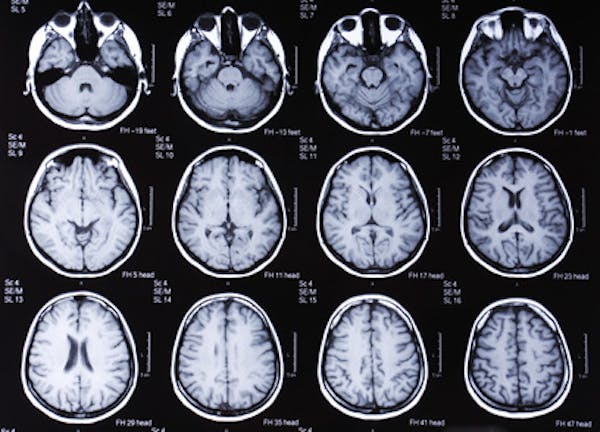

Uno studio condotto dall'Università della California, a San Diego, ha evidenziato che livelli elevati della proteina PHGDH sarebbero presenti nei malati di Alzheimer anche prima che si manifestino i primi segni della malattia. Lo studio è importante perché potrebbe identificare, con un semplice esame del sangue, la presenza della malattia nelle fasi iniziali, aumentando così le possibilità di ritardare o addirittura alleviare i sintomi. L'Alzheimer non ha ancora una cura, ma è già noto che adottare uno stile di vita più sano, stando attenti al corpo e alla mente, potrebbe contribuire a ritardare i sintomi cognitivi della malattia.

Guidata dai professori Sheng Zhong, Xu Chen e Riccardo Clandrelli, la ricerca, pubblicata sulla rivista Cell Metabolism, ha analizzato tessuti cerebrali umani e ha riscontrato un marcato aumento nell'espressione del gene PHGDH negli individui con Alzheimer. Oltre ad indicare la possibilità di una diagnosi precoce della malattia, uno dei principali avvertimenti della ricerca è la necessità di cautela nell'uso eccessivo della serina, sostanza prodotta dal PHGDH, ed essenziale per il metabolismo cerebrale. Ricerche precedenti hanno stimolato la convinzione che gli integratori che contengono l'aminoacido potrebbero aiutare a combattere la malattia. L'attuale studio, tuttavia, ha rilevato che, piuttosto che insufficiente negli individui con Alzheimer, la produzione di serina sarebbe stata in realtà eccessiva, il che sarebbe direttamente collegato a un peggioramento della funzione cerebrale.

Uno studio precedente, condotto due anni fa dallo stesso gruppo di scienziati dell’Università della California, aveva già indicato che il PHGDH potrebbe essere un biomarcatore sicuro per l'Alzheimer. All'epoca, i ricercatori hanno analizzato campioni di sangue di anziani e hanno riscontrato un marcato aumento dell'espressione del gene PHGDH sia nei pazienti di Alzheimer che negli individui sani fino a due anni prima che fosse stata diagnosticata la malattia.

Nella stessa ricerca fu notato anche che i livelli di espressione di PHGDH sarebbero cresciuti di più nel corso della malattia, com’era già stato osservato in studi simili con topi. Con gli umani, gli scienziati hanno confrontato la quantità dell'enzima nel sangue di pazienti con diagnosi di Alzheimer con punteggi ottenuti in base a due diverse valutazioni cliniche: una che valuta la memoria e le capacità cognitive e l'altra, la gravità della malattia in base a cambiamenti nel cervello. I risultati hanno dimostrato che più bassi sarebbero i punteggi, maggiore sarebbe l'espressione di PHGDH nel cervello.

Dagli studi e dai risultati, si spera che alla fine si possa arrivare a un modo più semplice per diagnosticare l'Alzheimer, attraverso un esame del sangue, ad esempio. È già noto che i cambiamenti cerebrali causati dalla malattia possono verificarsi persino decenni prima della comparsa dei sintomi. Una diagnosi più semplice e precoce renderebbe più facile monitorare la malattia e consentirebbe agli scienziati di testare i trattamenti in fasi molto precedenti, quando potrebbero essere più efficaci.